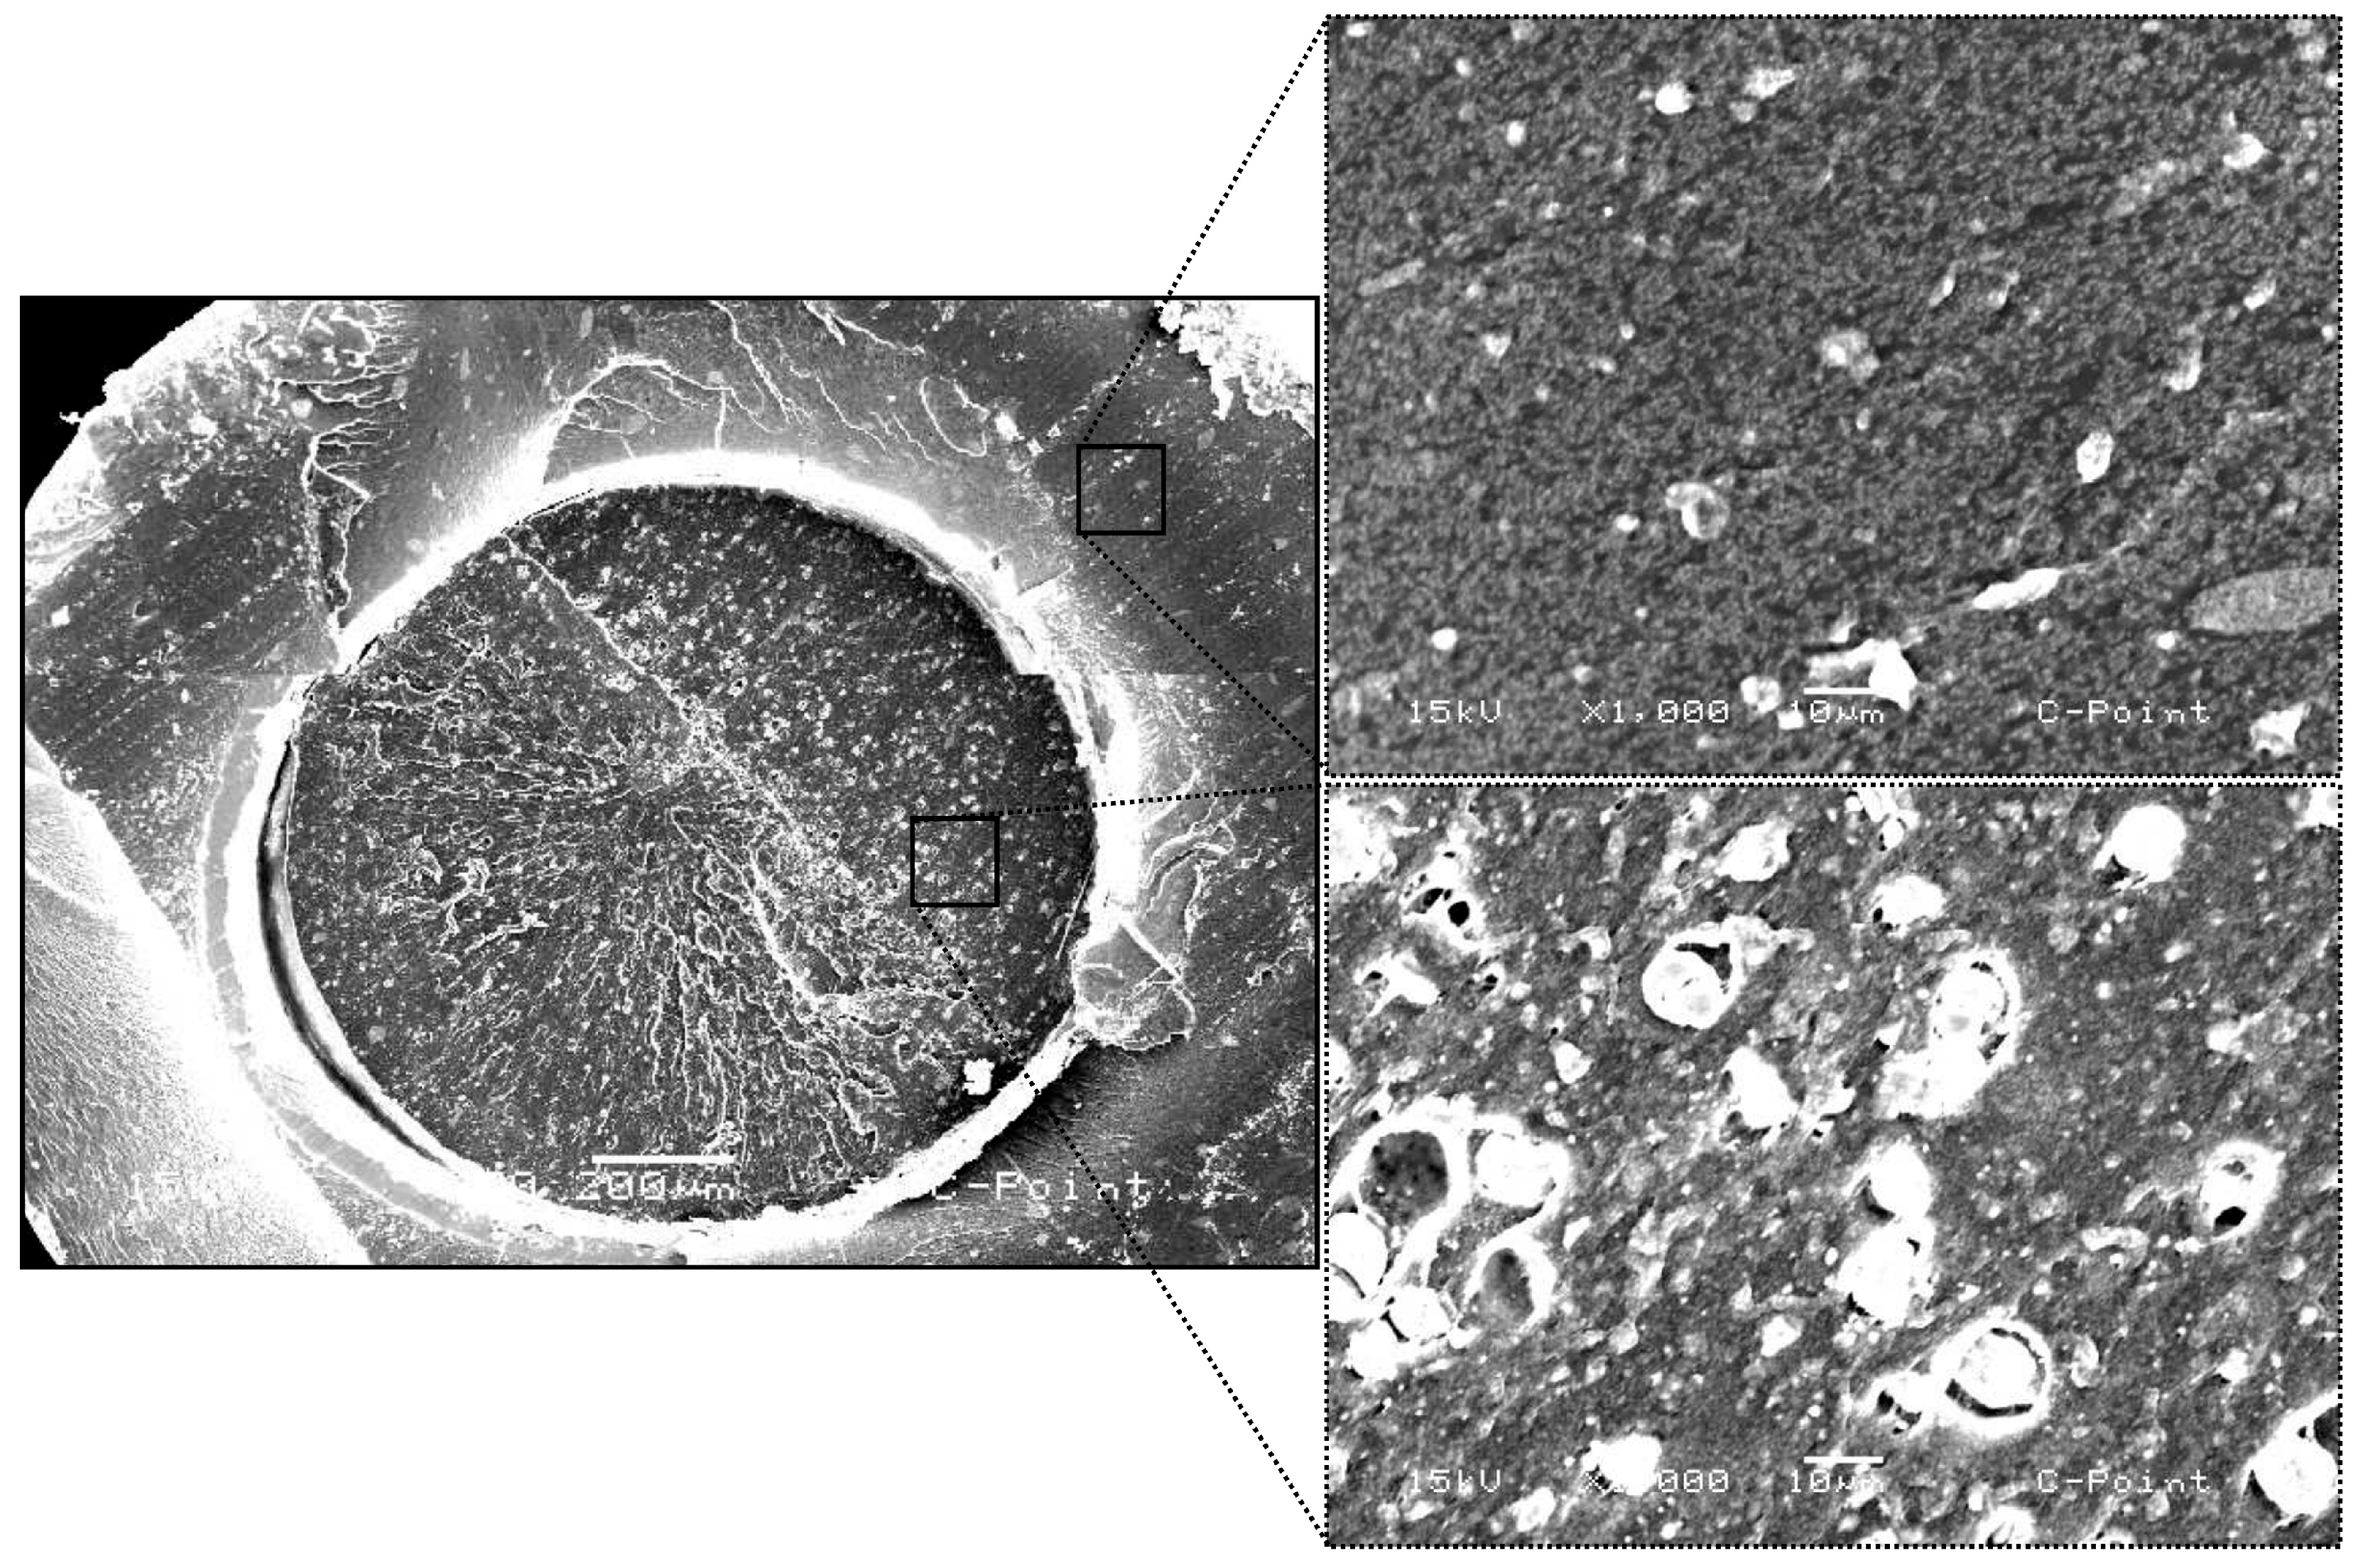

The scanning electron microscopy (SEM) images illustrate the structural characteristics of C-Point (Figure 3). In the low-magnification micrograph (70), a transverse section of the cone is displayed, revealing its layered architecture. The outer layer appears distinct from the inner core, suggesting potential differences in composition or porosity. At higher magnification (1000), detailed images of both the outer and inner layers are provided. The outer layer exhibits a relatively dense and homogeneous texture, whereas the inner region presents a more porous structure.

The samples were chemically evaluated using the SEM/EDS technique to demonstrate the importance of the chemical characterization of the materials, compared to the biological analysis performed. Scanning electron microscopy (SEM) analyses revealed significant structural differences between C-Point and conventional gutta-percha. In cross-section, C-Point presents a layered structure with a denser external surface and a less compact internal region composed of materials of different natures. This arrangement and the special composition of C-Point allow it to expand laterally when exposed to moisture, promoting better sealing of the root canal, as indicated in studies [26]. This technology is justified considering that endodontic success depends on adequate sealing, blocking bacterial infiltration and reducing the risk of periapical inflammation [23,27].

Figure 3. Scanning electron microscopy (SEM) images of the C-Point endodontic obturation cone, showing its layered structure. The low-magnification image (70) reveals the distinct outer layer and inner core, suggesting differences in composition or porosity. Higher magnification (1000) highlights the dense and homogeneous texture of the outer layer, contrasted with the more porous inner region.